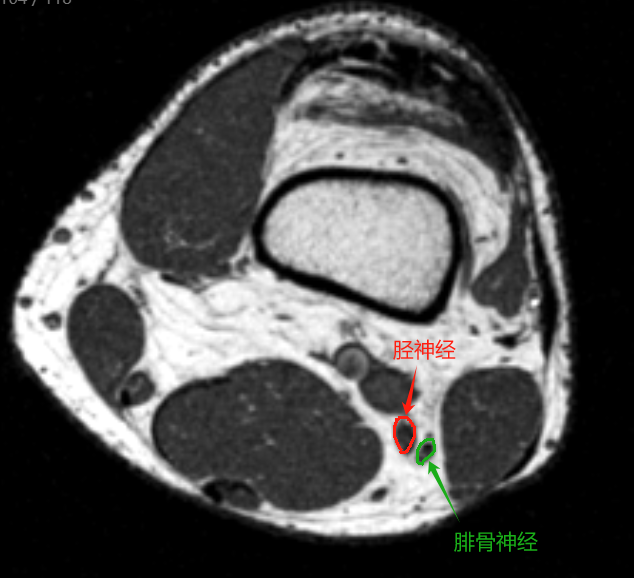

MRI断层解剖(膝关节)轴位为水平切面,从股骨远端至胫骨近端,重点显示以下结构:

1. 韧带与肌腱

• 前交叉韧带(ACL):外侧髁间嵴至股骨外侧髁内侧面,轴位呈束状低信号。

• 后交叉韧带(PCL):胫骨后方至股骨内侧髁,轴位为卵圆形低信号结构。

• 内侧副韧带(MCL):分浅深两层,浅层为条带状低信号,深层与关节囊融合。

• 外侧副韧带(LCL):条索状低信号,连接股骨外上髁与腓骨头。